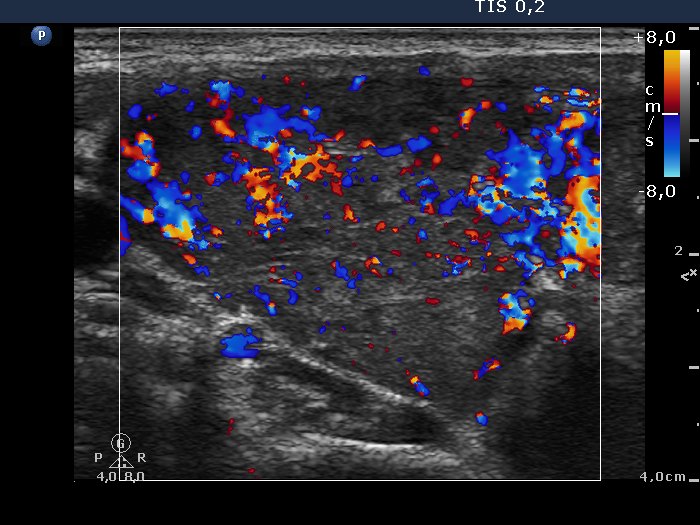

Ultrasonography: The thyroid was hypoechogenic and contained numerous discrete echonormal lesions divided by fibrous tissue. The vascularization was increased.

The sonographic pattern corresponds to the so-called micronodular (or pseudonodular) form of lymphocytic thyroiditis.